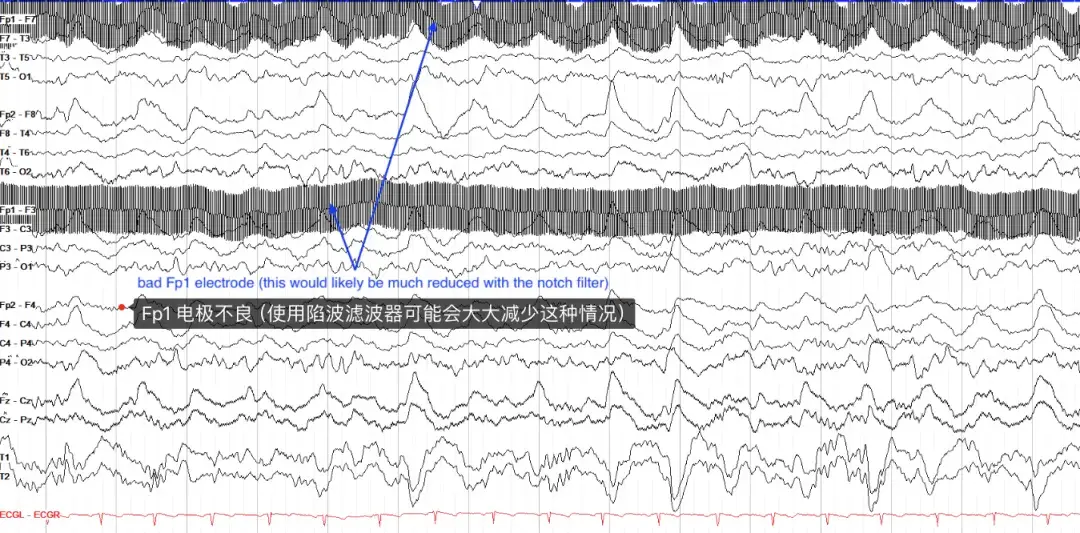

电伪影最常见的原因是通过电线传输的 60 Hz (如美国)电活动(某些地区为 50 Hz,如欧洲等)的干扰。当然,电伪影是一种非常快速、非常单调的活动,可以使用陷波滤波器选择性地去除 60Hz 的所有 EEG 活动(这不会影响对信号的解释,因为头皮 EEG 上没有大脑活动那么快)。在下面的示例中,陷波滤波器未打开,并且 Fp1 电极可能不太正确,导致大量电气干扰。